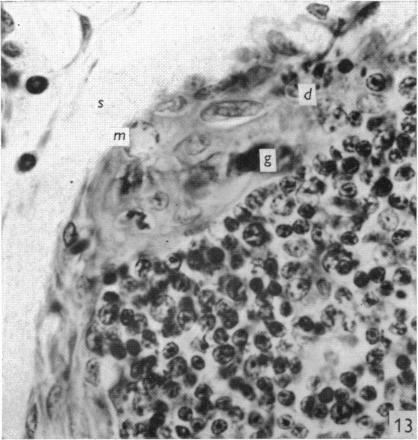

The effect of castration, oestrogens, testosterone and the oestrous cycle on the cortical epithelium of the thymus in male and female rats.

J Anat. 1968 Jun;103(Pt 1):113-33.